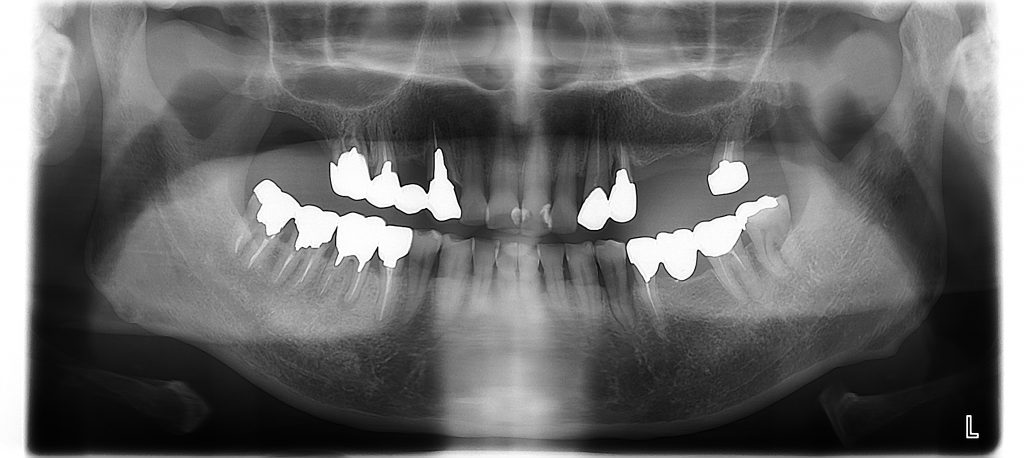

最初いらしたときのお口のレントゲン写真です上の歯は歯周病で抜かなければいけないのが1本、割れている歯が2本ありました。下の歯に比べ、上の歯は骨が柔らかくダメになりやすい事があります。

処置前